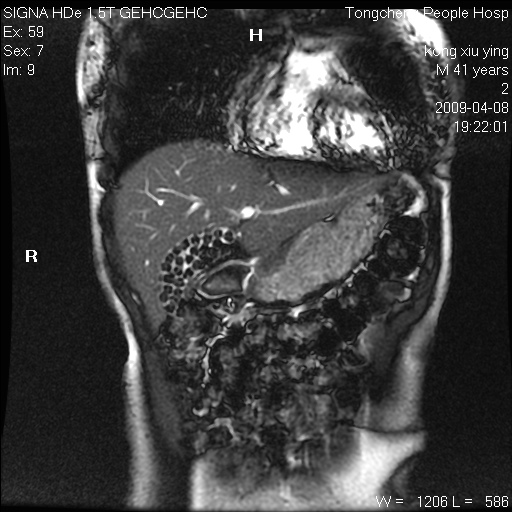

标题: CL1008:【经典】胆囊石榴籽样结石。

女,41岁。健康体检——彩超提示:胆囊显示不清。平素健康,无不适感。

腹部mr扫描及mrcp,图像如下: